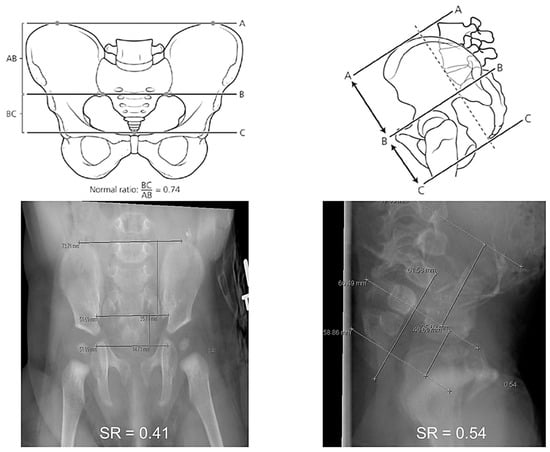

- Ahmad, H.; Halleran, D.R.; Stanek, J.R.; Thompson, B.P.; Bates, D.G.; Rusin, J.A.; Minneci, P.C.; Levitt, M.A.; Wood, R.J. Correlation between the Lateral and Anteroposterior Sacral Ratios in Anorectal Malformations. Pediatr. Radiol. 2021, 51, 1867–1872. [Google Scholar] [CrossRef]

- Metzger, G.; Cooper, J.N.; Kabre, R.S.; Mak, G.Z.; Halleran, D.R.; Boyd, K.; Chan, S.; Corea, D.; Dydynski, P.; Gill, K.; et al. Inter-Rater Reliability of Sacral Ratio Measurements in Patients with Anorectal Malformations. J. Surg. Res. 2020, 256, 272–281. [Google Scholar] [CrossRef]

- Krois, W.; Palmisani, F.; Gröpel, P.; Feil, P.; Metzelder, M.L.; Patsch, J.M.; Reck-Burneo, C.A. Assessment of Sacral Ratio in Patients with Anorectal Malformations: Can Magnetic Resonance Imaging Replace Conventional Radiograph? J. Pediatr. Surg. 2021, 56, 1993–1997. [Google Scholar] [CrossRef]